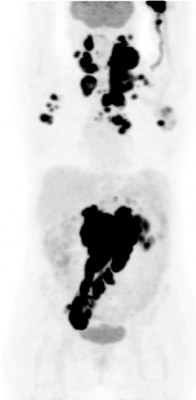

| Патологические очаги при лимфоме | Норма |